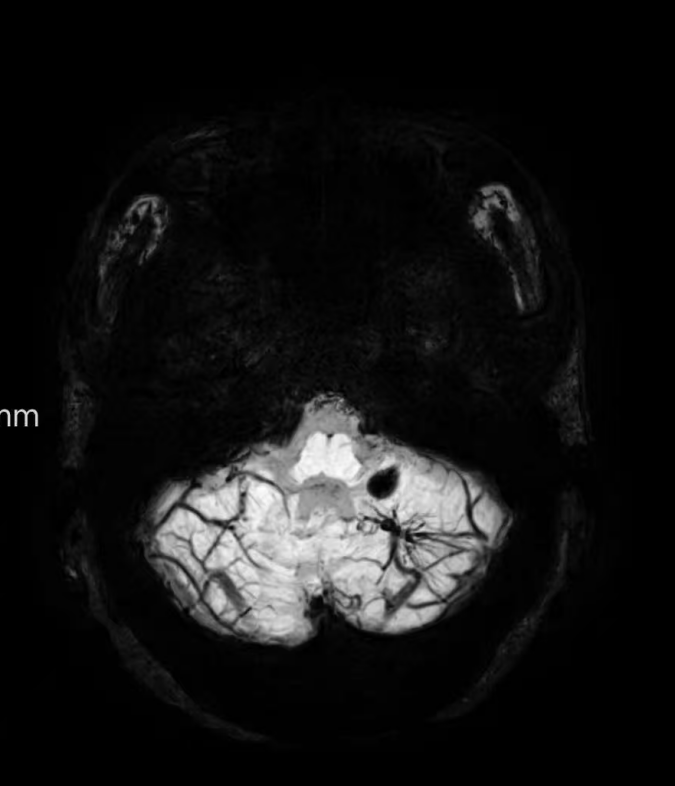

臨床中遇到一位患者,中年女性,反復(fù)出現(xiàn)頭痛,時(shí)輕時(shí)重,常規(guī)CT及磁共振檢查無(wú)明顯異常發(fā)現(xiàn),最后建議加做一個(gè)磁共振磁敏感加權(quán)成像(SWI),結(jié)果發(fā)現(xiàn)是左側(cè)小腦發(fā)育性靜脈畸形(DVA),SWI清晰顯示畸形的靜脈及周圍含鐵血黃素沉積;如下圖。這正是她頭痛的原因。

①診斷靜脈畸形:SWI能高精度地顯示發(fā)育性靜脈畸形——一種常見(jiàn)的腦血管畸形。在SWI上,發(fā)育性靜脈畸形會(huì)呈現(xiàn)典型的“海蛇頭”或“水母頭”征,即一堆細(xì)小的髓靜脈匯入一支粗大的引流靜脈。